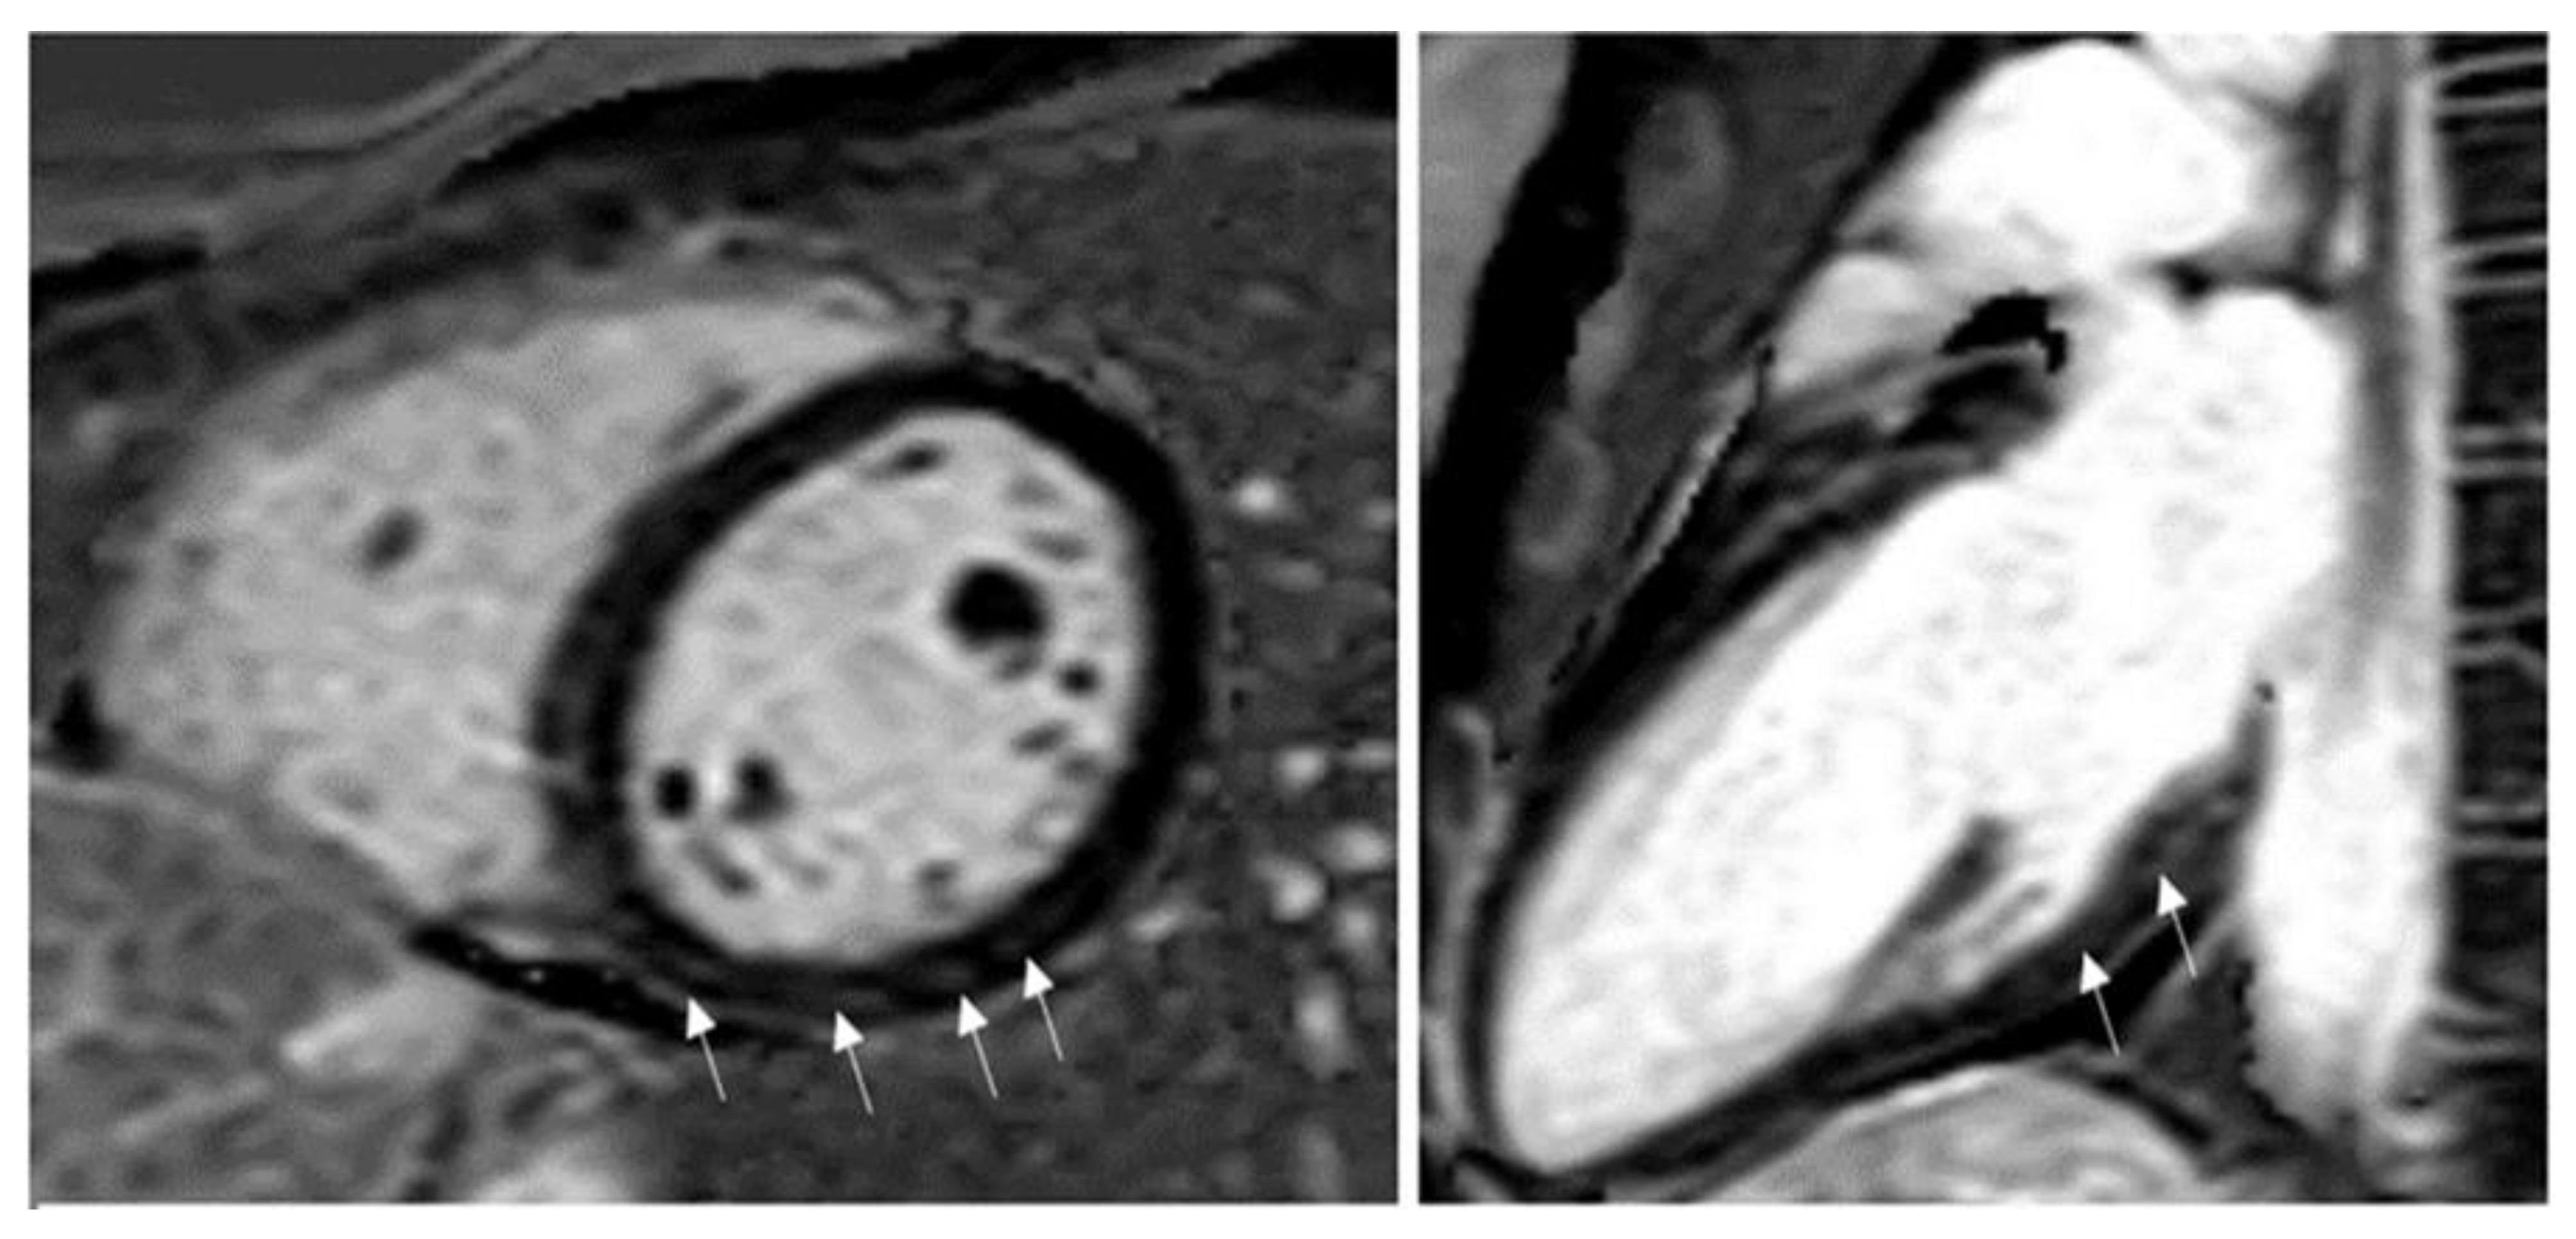

2. CMR Findings of Myocardial Inflammation and Pathological Correlations

3. CMR in Acute Myocarditis